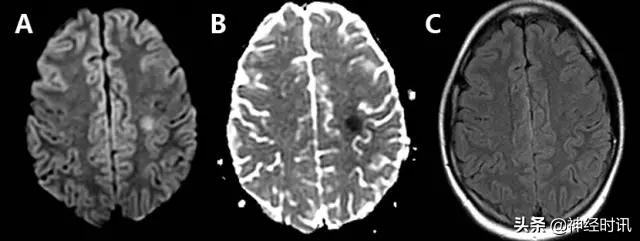

多发性硬化

多发性硬化可因突发性局灶性神经功能障碍(如失语或偏瘫)而就诊。其典型MRI表现为脑室周围白质、深部白质和皮质旁出现T2高信号病灶。急性病变通常伴有弥散增加,但其偶尔可能会显示为一过性(2~7天)弥散受限(图20)。弥散受限通常见于病变的边缘,但也可能是中心性的。这些病变大多伴有与亚急性卒中类似增强现象,提示为活动性炎症。少突胶质细胞、髓鞘和轴突等由于兴奋性毒性损伤所致的细胞毒性水肿,可能是此类患者发生弥散受限的原因。

图20 一例21岁女性复发-缓解型MS患者,17岁时为评估其轻微脑震荡综合征而进行的首次MRI检查偶然发现多发性硬化。其表现为:幕上存在以特征性模式分布的多发性T2高信号病灶(C:FLAIR),且右额叶白质存在一个弥散受限病变(A:DWI,B:ADC)。